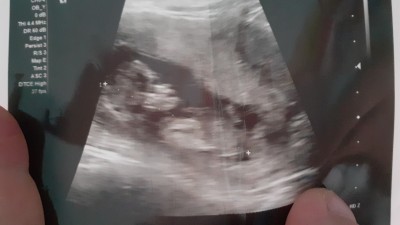

13+haftalık ilk oğlum var buda kıza benziyo çok hareketli göstermiyor dedi özelde doktorum

Gebelik haftası 13+23